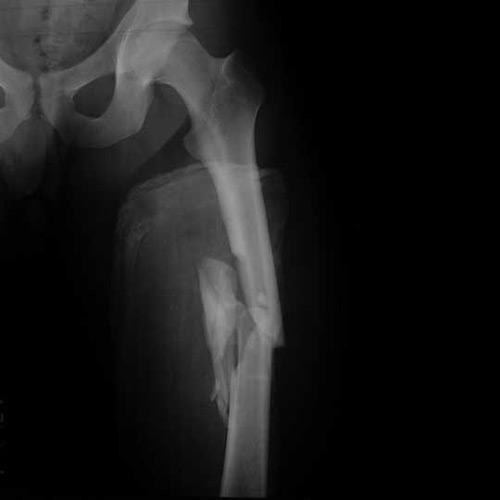

Смещение отломанных мелких частиц отличается разнообразием: в боковом направлении, в длину, под наклоном и ротационное, которые зависят от месторасположения травмы в диафизе. Таким образом, при правмировании в верхней 1/3 центральная отломанная частица отклоняется вперед и кнаружи. Отдаленный отломок под воздействием мышцы- супинатора — внутрь и кзади. Все эти механизмы вызывает клиническое деформирование по типу галифе.

Повреждение в нижней части вызывает следующее отклонение: центральный отломок под воздействием мышцы-супинатора отклоняется внутрь, а периферический — под воздействием мышцы-пронатора (икроножной) в заднем направлении.

Обязательно осмотр пациента завершается рентгенографическим исследованием с целью уточнения характера повреждения и диспозиции отломков.